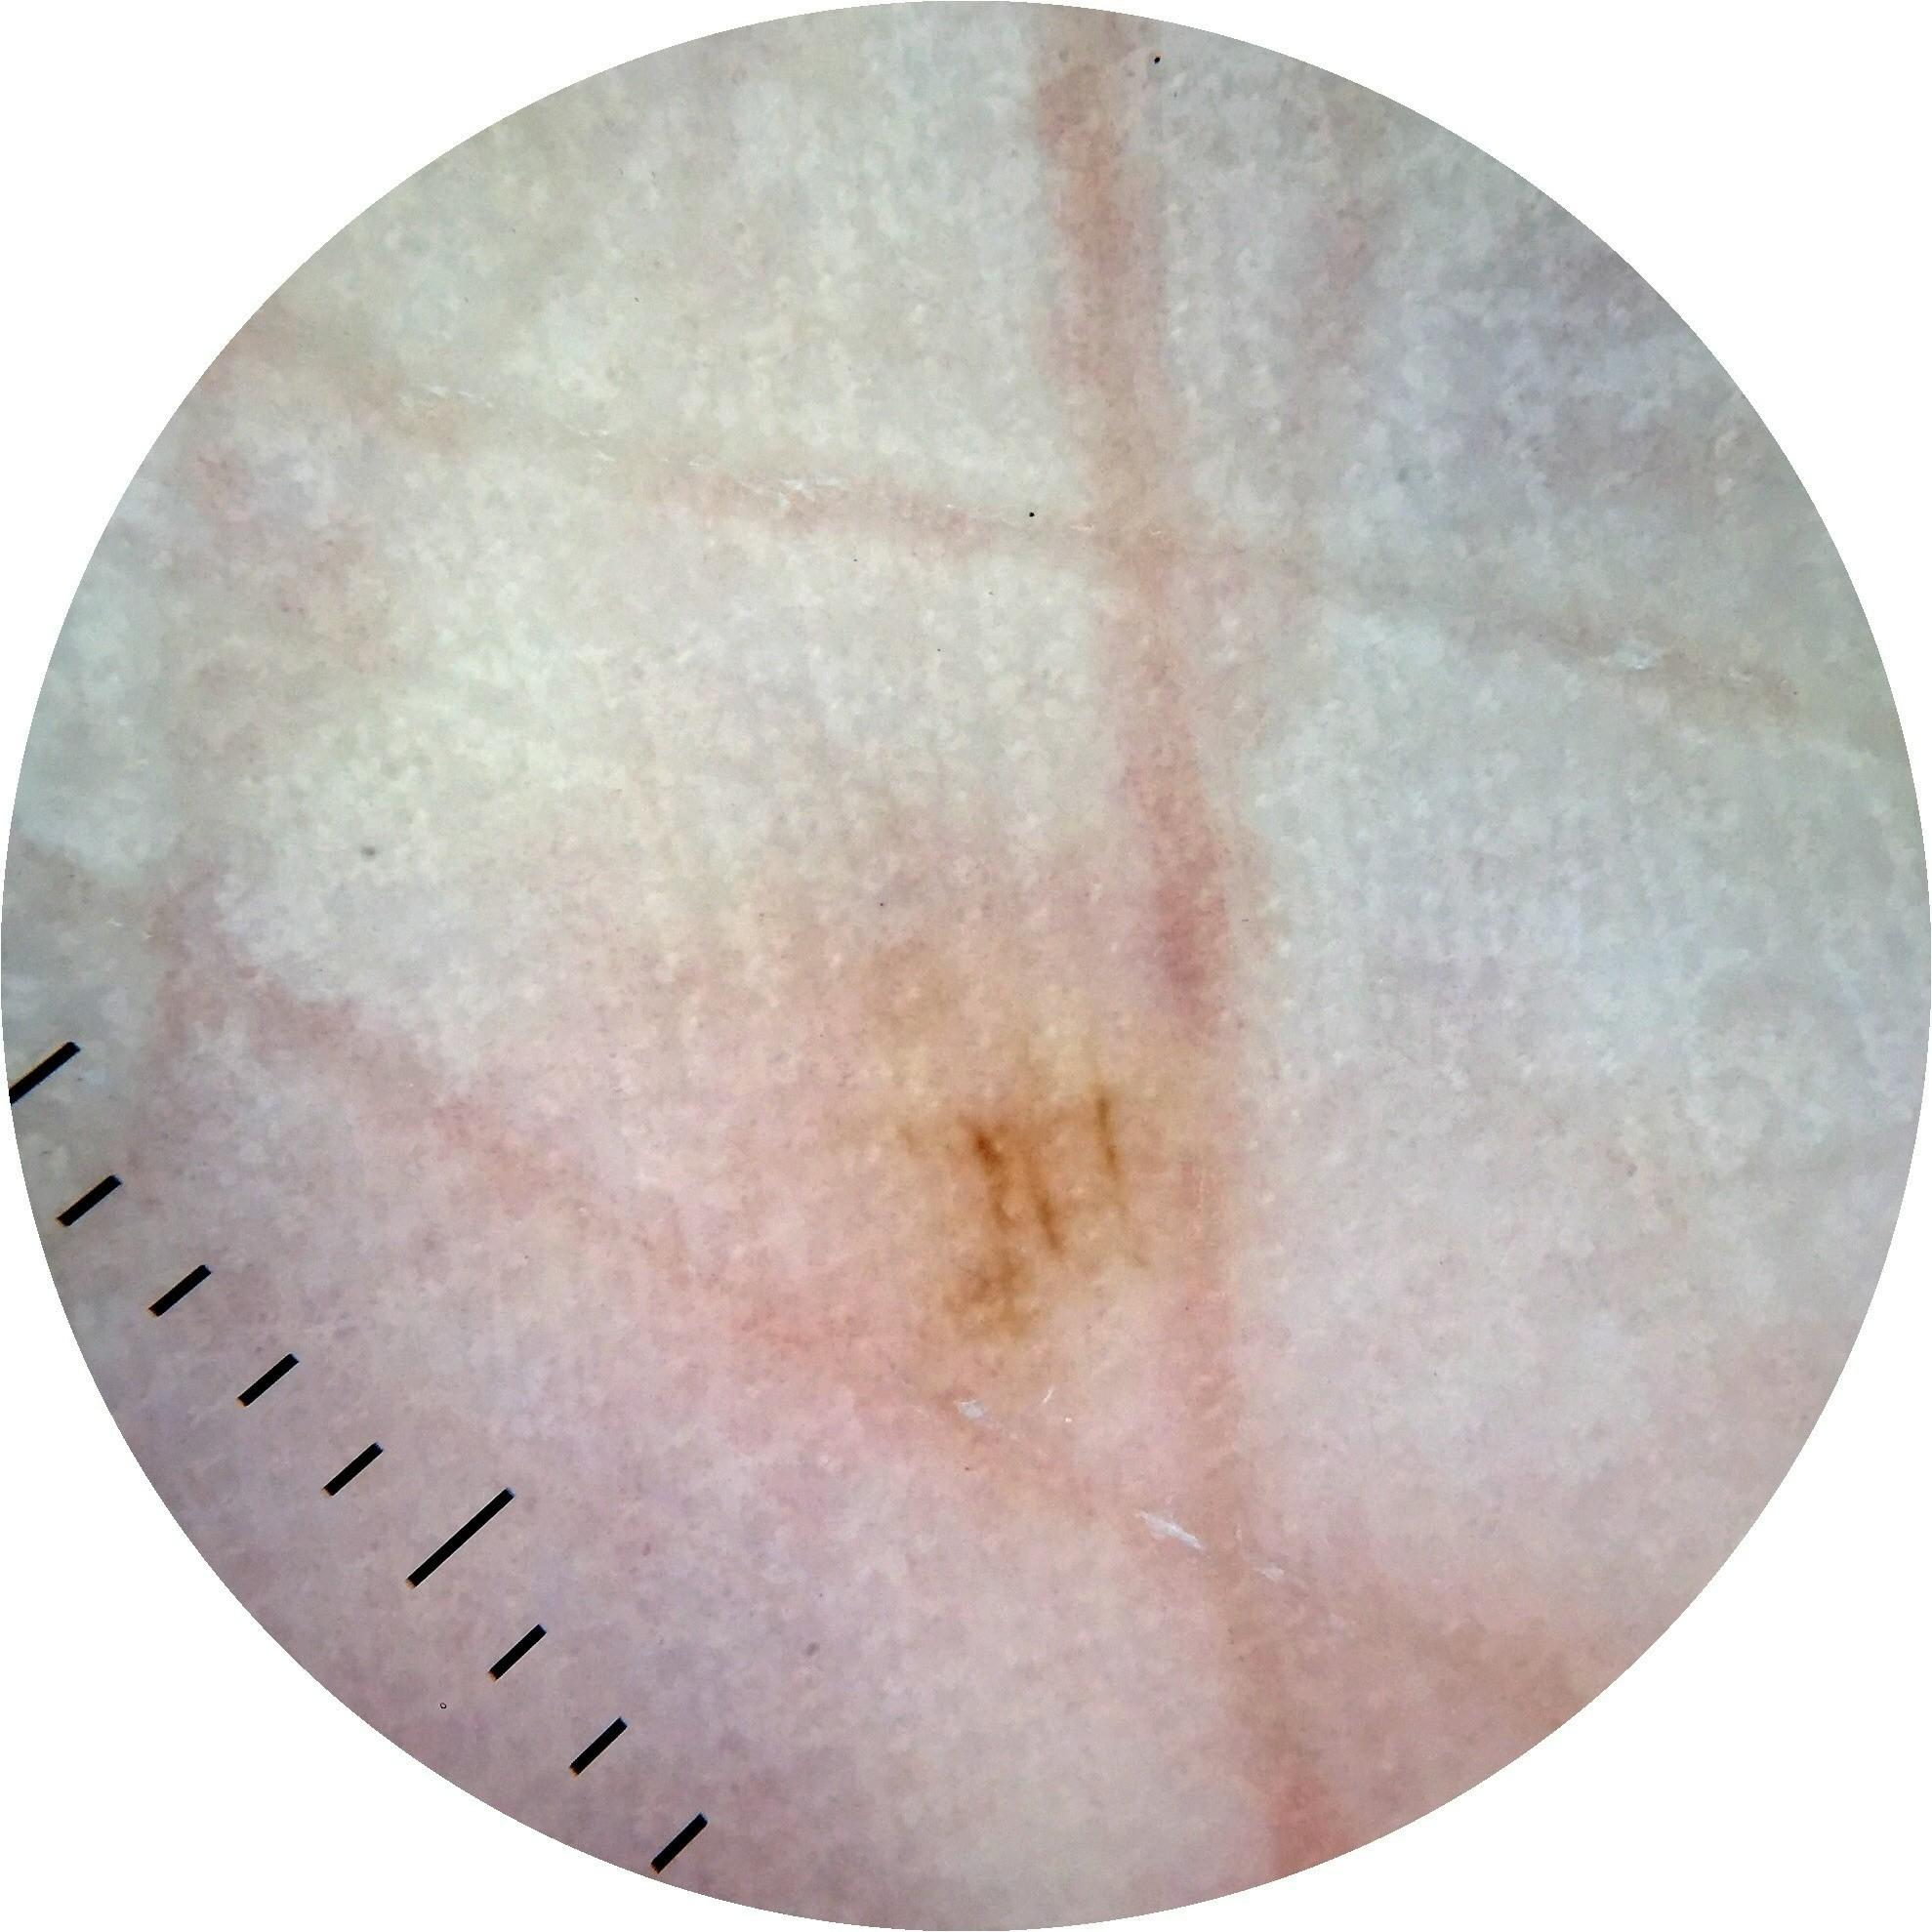

ISIC_7213120

Clinical

Field Value

acquisition_day 277

age_approx 70

anatom_site_1 Lower extremity

anatom_site_general lower extremity

diagnosis_1 Benign

family_hx_mm True

fitzpatrick_skin_type I

image_manipulation instrument only

image_type dermoscopic

lesion_id IL_3605610

patient_id IP_0257923

personal_hx_mm True

sex female